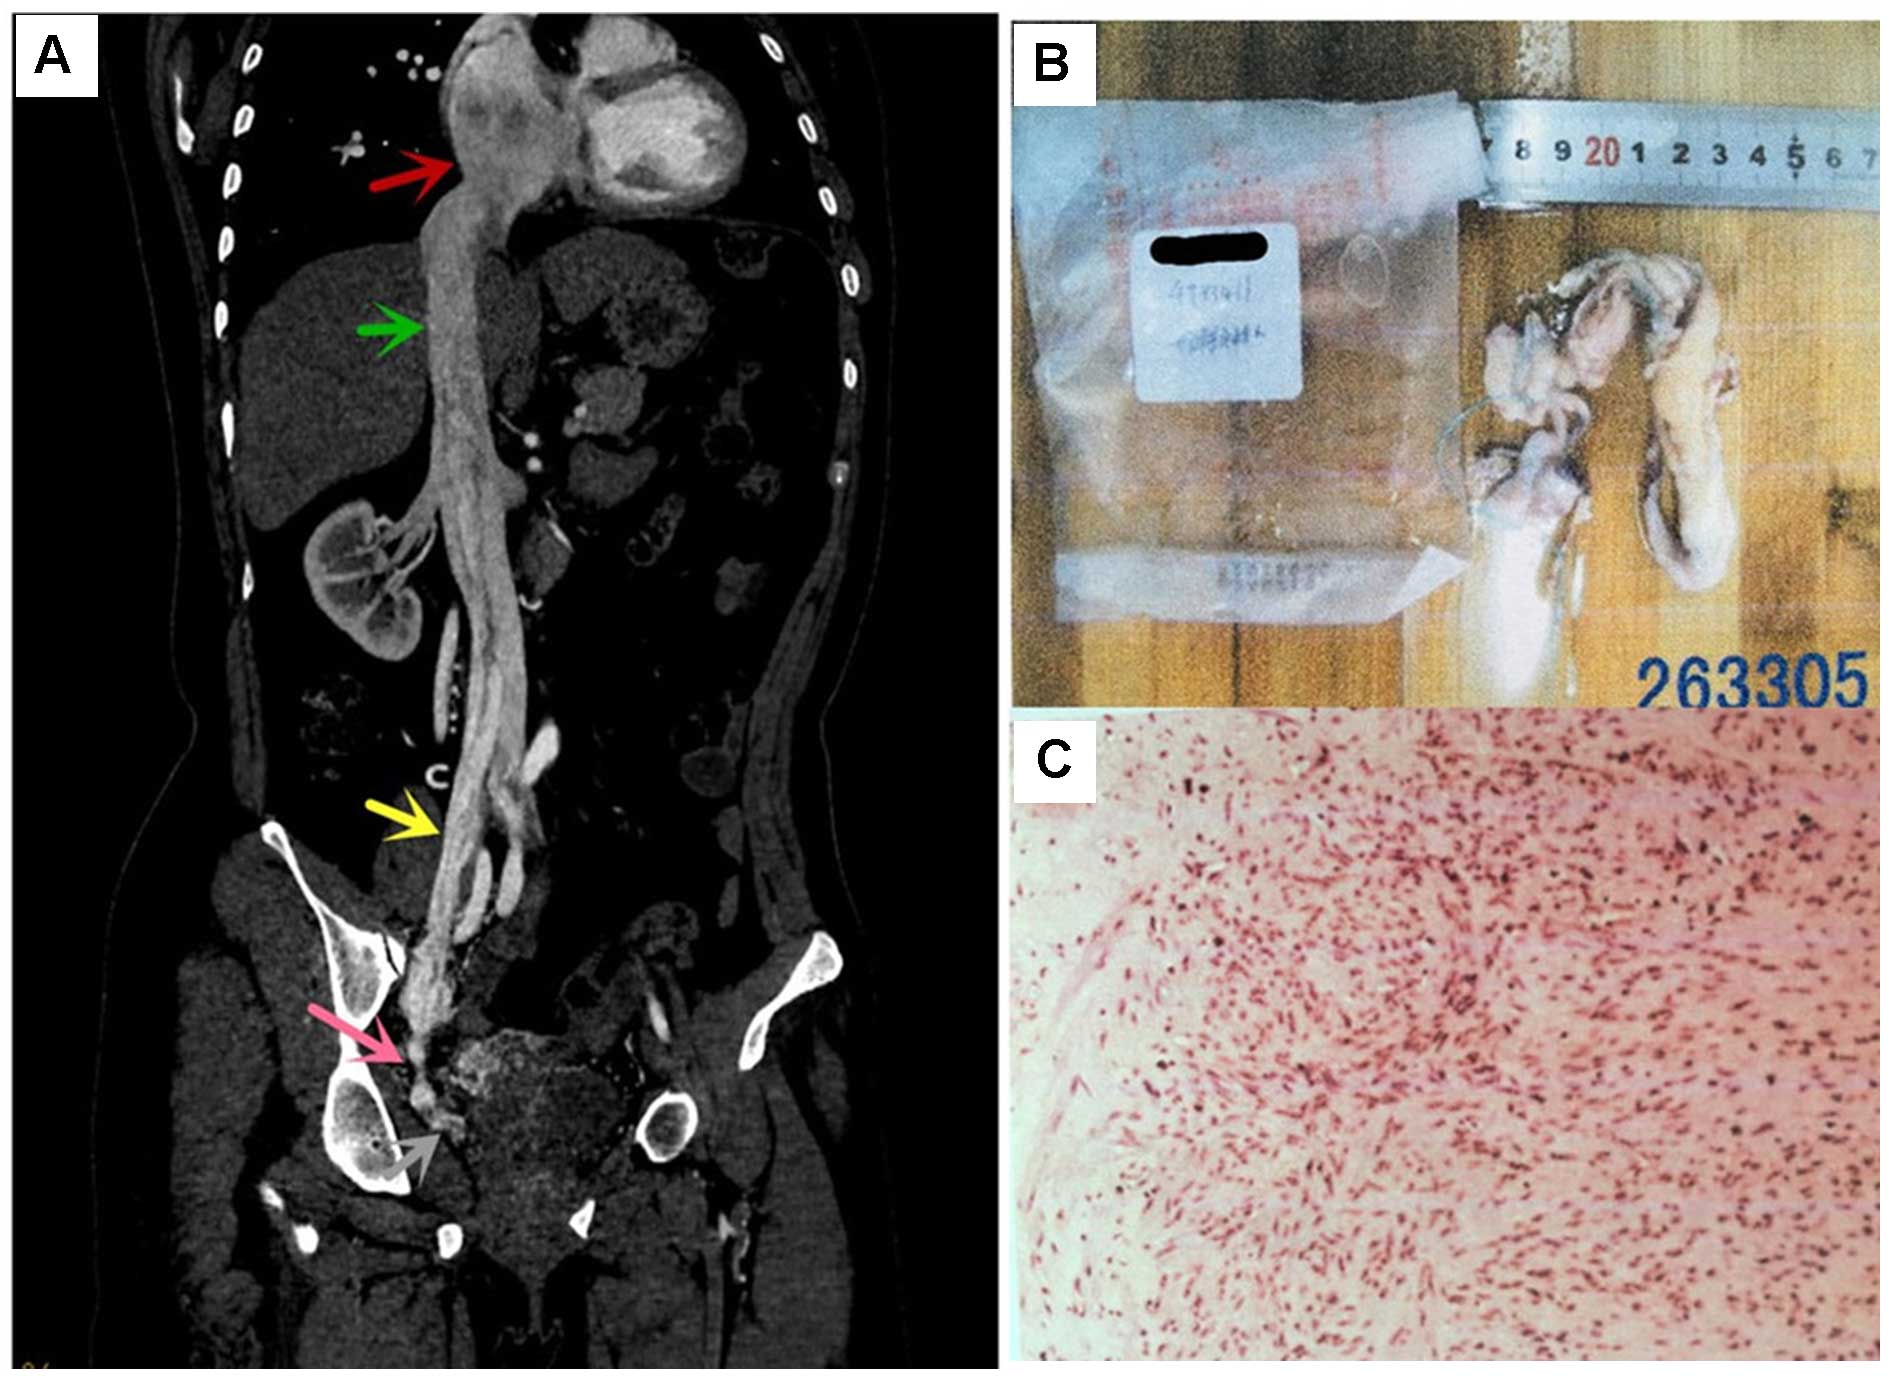

Intravenous leiomyomatosis with right atrium extension in two patients: A case report

Intravenous leiomyomatosis (IVL) is a rare benign tumor of the uterus mesoderm, which can spread via the vein, from the micro‑vein to the inferior vena cava, and even to the right atrium. IVL was first described this disease in 1896 and the first presented case of IVL with right atrium extension in the autopsy was described in 1907. On rare occasions, the tumors may extend into the regional and systemic veins, thus reaching the heart. This may subsequently cause intracardiac leiomyomatosis (ICL), which may lead to congestive heart failure and on occasion, sudden fatalities. Due to its rarity and diffuse symptoms, the misdiagnosis of ICL is common and as a result, the condition may be under‑reported. The present study reported two cases of IVL resected at the General Hospital of Shenyang Military Command. A hysteromyomectomy for uterine fibroids was performed on each patient (Case 1, 41 years ago; Case 2, 3 years ago). One patient presented with chest pain following a period of activity and the other presented with heart neoplasm during a routine health examination.

Figure 1

Figure 2